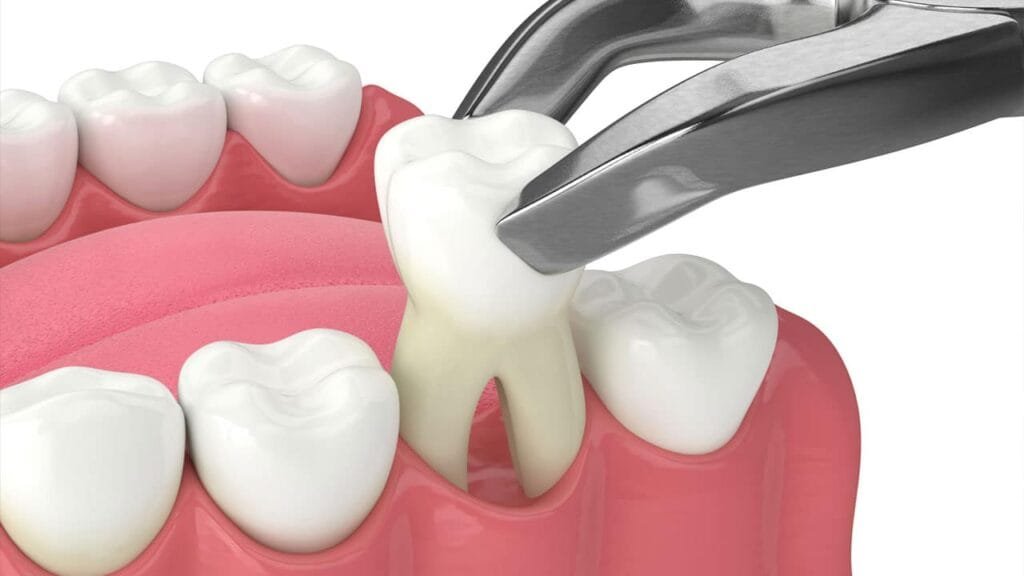

একটি আত্মবিশ্বাসপূর্ণ হাসি আপনার জীবন বদলে দিতে পারে। কিন্তু যদি দাঁতের অভাব আপনাকে পিছনে টানে? তাহলে, ডেন্টাল ইমপ্ল্যান্ট এর মাধ্যমে আপনার হারিয়ে যাওয়া হাসিকে ফিরে পান। ডেন্টাল ইমপ্লান্ট হল একটি স্থায়ী এবং প্রাকৃতিক সমাধান যা হারিয়ে যাওয়া দাঁত প্রতিস্থাপনের জন্য ব্যবহৃত হয়। ডাঃ অনুরাধা বোস ডেন্টাল ক্লিনিকে, আমরা আপনাকে আরামদায়ক,দীর্ঘস্থায়ীএবং উন্নত ডেন্টাল ইমপ্লান্ট চিকিৎসা প্রদান […]